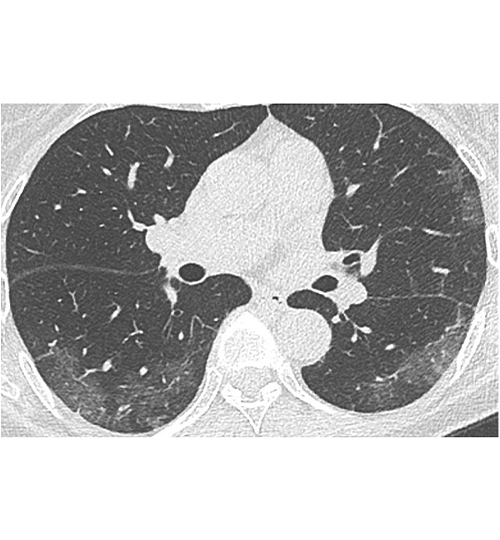

Image : Tomodensitométrie. Patiente de 71 ans sans antécédent, atteinte de Covid-19, ayant une pneumopathie interstitielle. Aspect typique initial : atteinte bilatérale à type de verre dépoli périphérique sous-pleural. Crédit : Société française de radiologie (https://bit.ly/39NaivY).